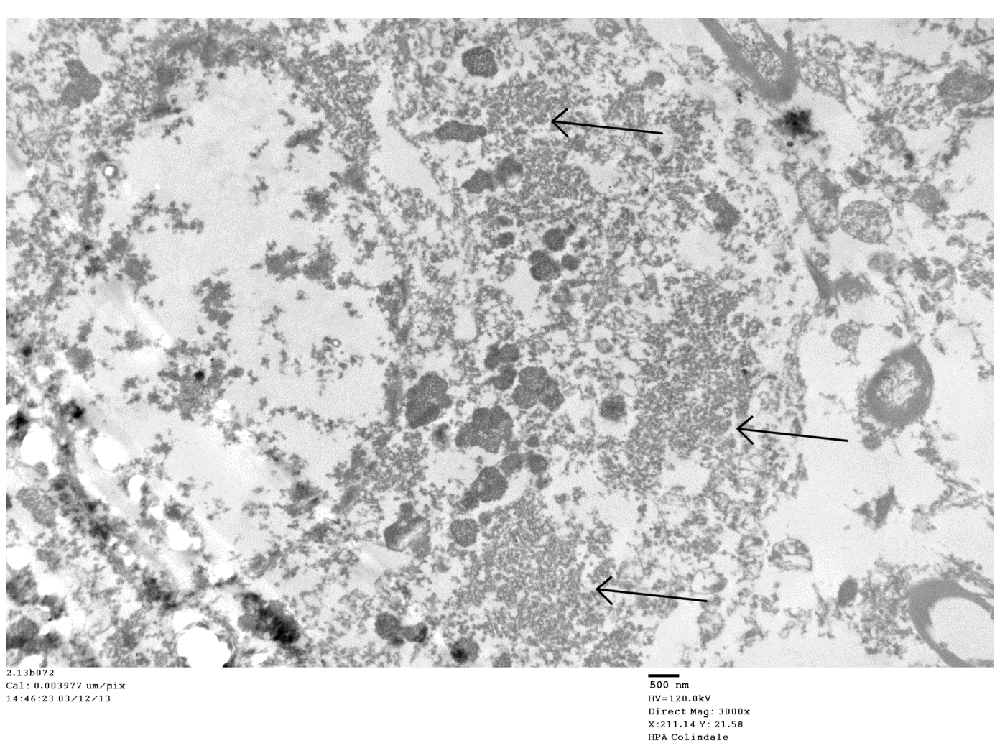

TEM changes were observed in the brainstem neurons in the PD cases and in the spinal cord motor neurons in the poliomyelitis cases. TEM of PD neurons at low magnification showed advanced apoptosis. There were almost ‘empty’ nuclei with clumped chromatin and multiple cytoplasmic virus factories. Few cytoplasmic organelles remained (Figure 1 and Figure 2). VLP were found by TEM in the nuclei and cytoplasm in the neurons of all the PD cases studied. The VLP were similar in morphology to the VLP we described in the brain of encephalitis lethargica, which had been confirmed to be a strain of enterovirus by molecular analysis1. The cytoplasmic virus factories in PD neurons consisted of large numbers of VLP interspersed with irregularly shaped endoplasmic reticulum membranes and embedded in virus factory (Figure 3 and Figure 4). VLP were observed attached to the membranes (Figure 3). The average measurements of the cytoplasmic VLP in Figure 3 and Figure 4 were both 31 nm (Table 1). Cytoplasmic virus factories in other PD neurons consisted of incomplete VLP at an early stage of assembly (Figure 5, see Discussion).

Low magnification of a neuron in substantia nigra. Arrows point to virus factories.

This image shows cytoplasmic virus factories (arrows).